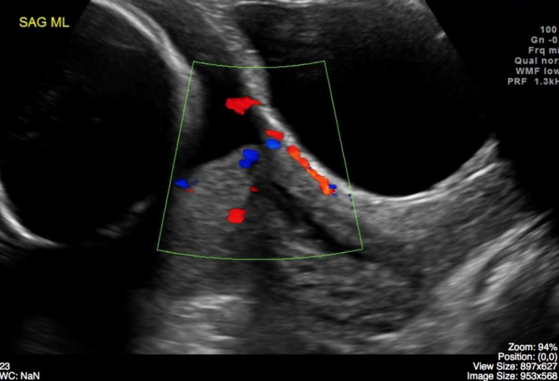

Ultrasound Detection: The primary method for identifying placenta previa during pregnancy.

Ultrasound Utilization: Gold Standard